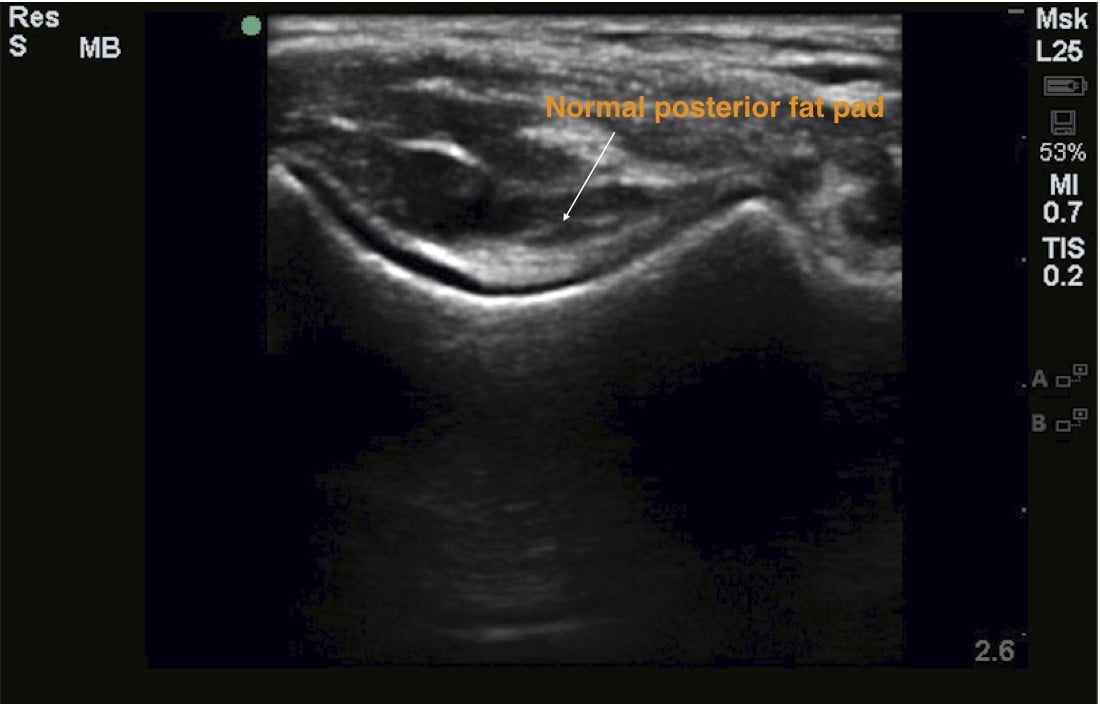

With the elbow bent at 90 degrees (Figure 1), use the linear probe in longitudinal (Figure 2) and transverse axes (Figure 3) to identify (a) distal humerus (b) olecranon (c) posterior fat pad

Figure 3: Transverse view of the olecranon fossa with normal posterior fat pad